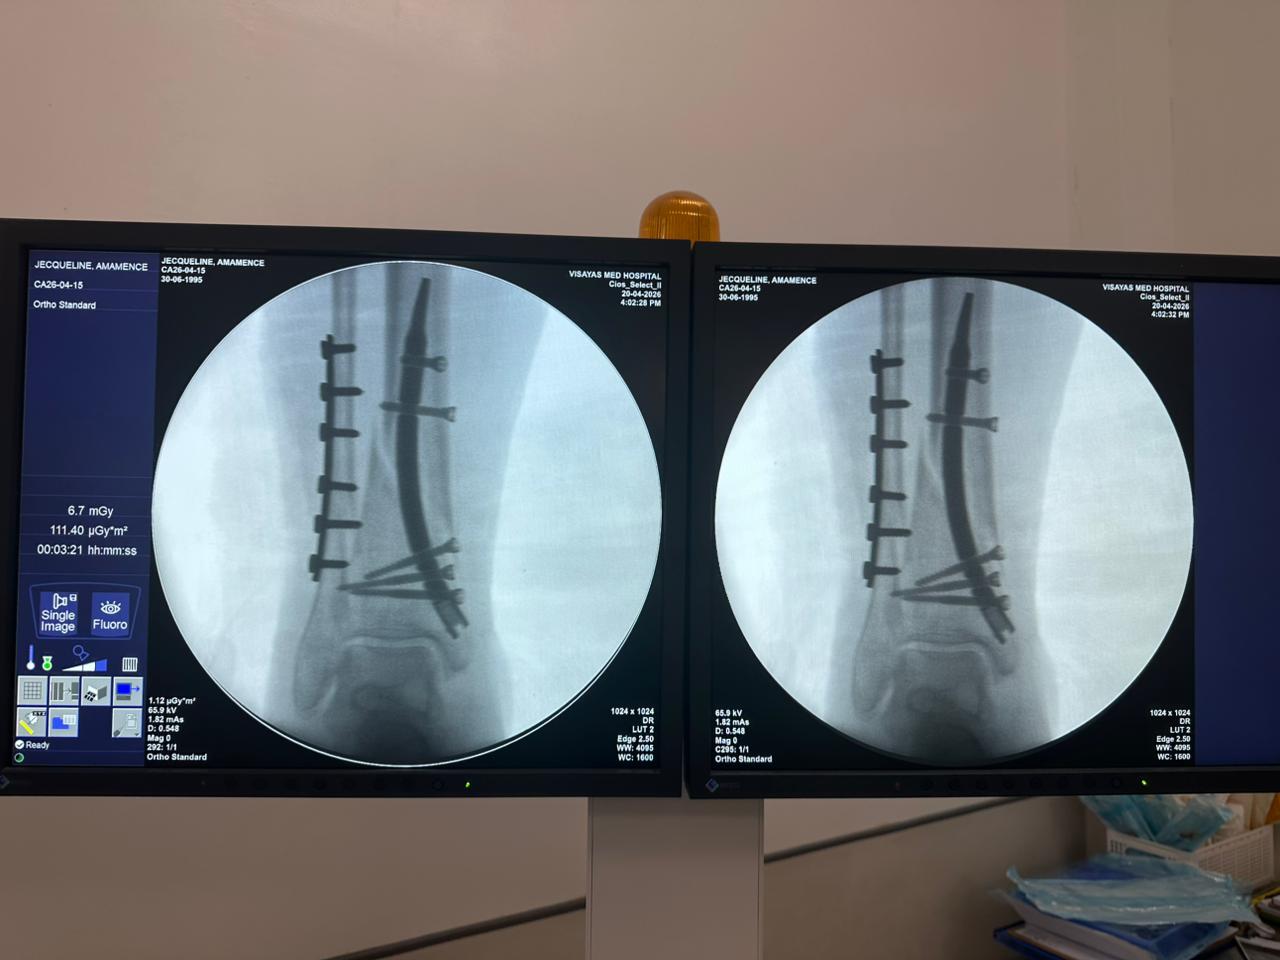

Caso di studio sulla fissazione del chiodo tibiale distale con supporto per placca peroneale

Paziente:

Paziente di 31 anni

Area Chirurgica:

Tibia e perone distali

Prodotto utilizzato:

Chiodo tibiale distale

Piastra di bloccaggio peroneale

Immagine:

Fluoroscopia intraoperatoria con arco a C, viste AP e laterali

Questo caso prevedeva la fissazione tibiale distale utilizzando un chiodo tibiale distale intramidollare. La fluoroscopia intraoperatoria ha confermato la posizione del chiodo, delle viti di bloccaggio distali e della fissazione della placca peroneale.